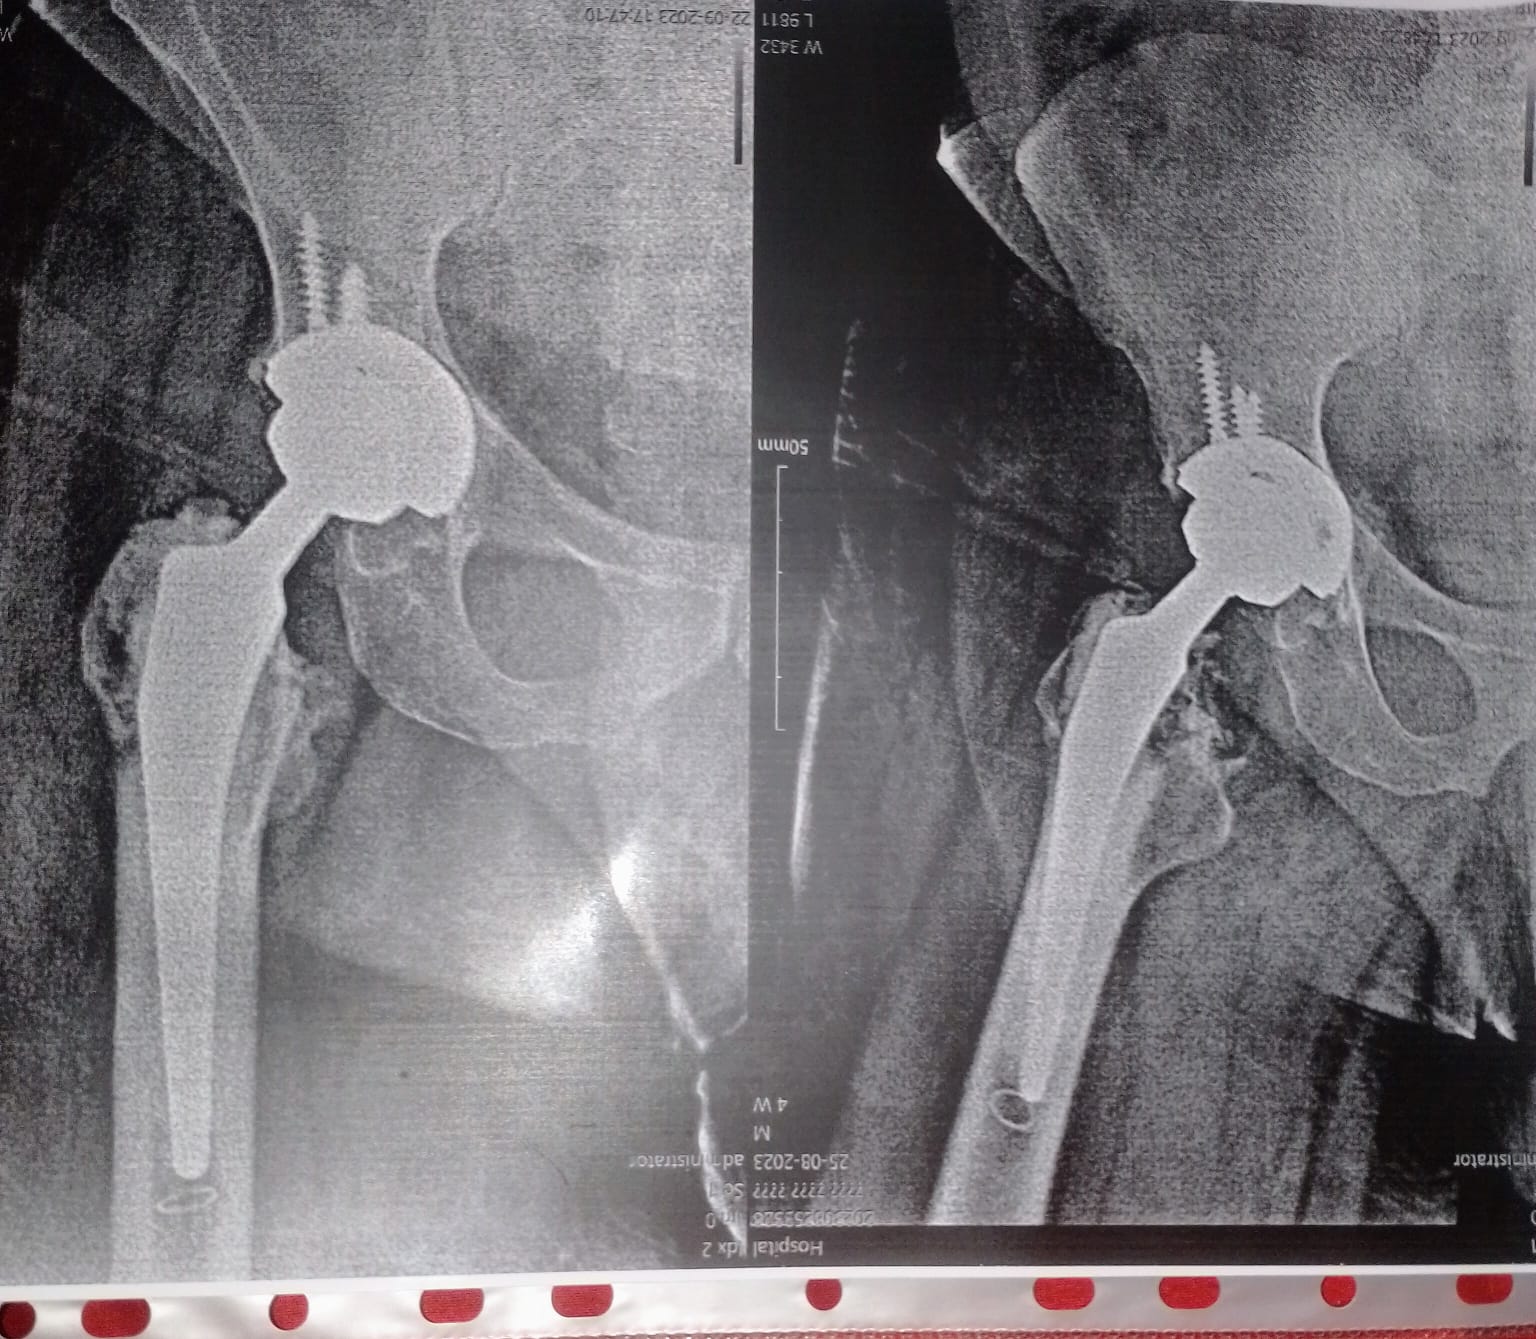

عملت عملية تركيب مفصل كامل للفخد